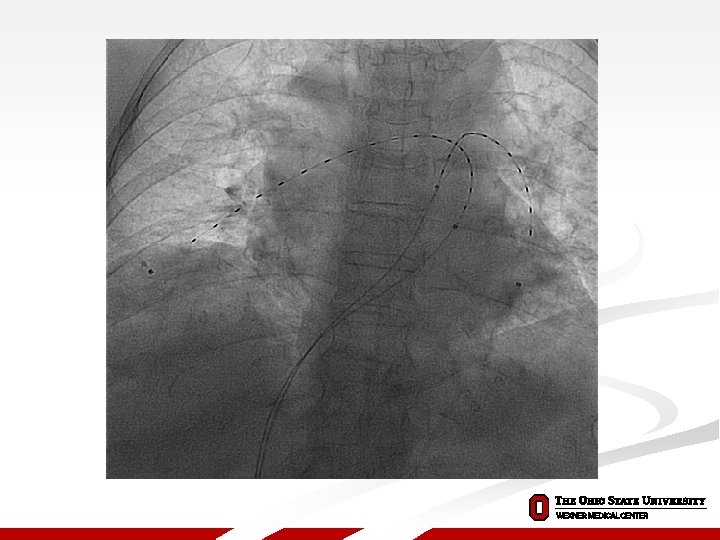

Treatment of High Risk patients The SEATTLE II Trial Standard Anticoagulation for PE UFH goal PTT 40 -60 sec during procedure Catheter Placement and Treatment Based on Extent of Disease Unilateral: 1 catheter infusing t-PA 1 mg/hour for 24 hours Bilateral: 2 catheters infusing t-PA 1 mg/hour/catheter for 12 hours Baseline Right Heart Catheter Measurements Including pulmonary artery systolic pressure Ultrasound-Facilitated, Low-Dose, Catheter-Directed Fibrinolysis t-PA Infusion Activation of high frequency, low power ultrasound Procedure Completion Post-Procedure Right Heart Catheter Measurements 34 Catheter Removal

Treatment of High Risk patients The SEATTLE II Trial Procedural Characteristics Mean dose of t-PA ± SD*, mg Successful device placement**, n (%) Access sites***, n (%) Right femoral vein Left femoral vein Right internal jugular vein Other Number of devices per patient*, n (%) 0 1 2 Completed infusion of t-PA***, n (%) 23. 7 ± 2. 9 278 (97. 5) 177 (63. 7) 61 (21. 9) 31 (11. 2) 9 (3. 2) 1 (0. 7) 20 (13. 3) 129 (86) 272 (97. 8) *N = 150 patients (1 patient died before devices could be placed) **N = 285 devices attempted ***N = 278 devices placed 35